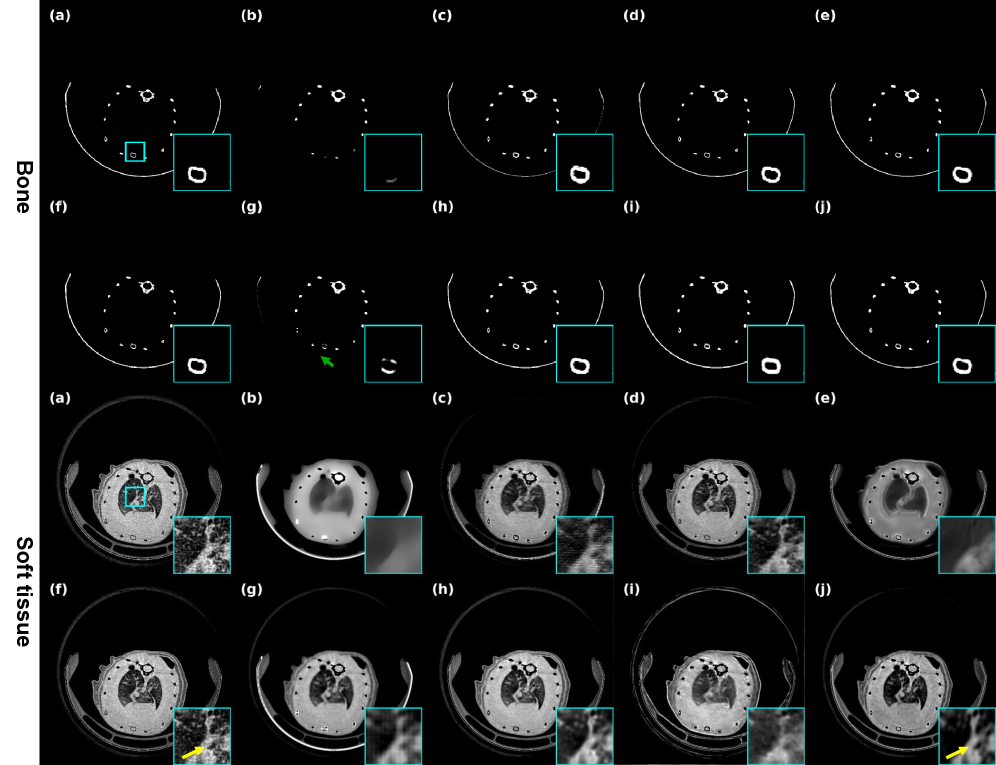

4.1.4 Mouse dual-energy photon counting CT dataset

Conducted jointly with the Institute of High Energy Physics (IHEP), Chinese Academy of Sciences, this work examined how EGenDiff can be extended to PCCT imaging. As shown in Fig. 5, dual-energy mouse CT data were acquired using the Color SA system developed by the IHEP, Chinese Academy of Sciences. Each scan acquired projections with a dimension of , covering energy ranges of and . Scanning parameters included: source-to-object distance , source-to-detector distance , and pixel size . The device uses an advanced photon counting detector with a spatial resolution of up to 15 . It is mainly used for live animal CT imaging in preclinical experimental studies, and can now be applied to whole-body structural energy spectrum imaging of various rodents. PCCT is inherently challenging yet beneficial: It enables precise utilization of both low-energy and high-energy spectral data. Specifically, low-energy scans provide high contrast and improved material differentiation, whereas high-energy data help mitigate beam hardening and metal artifacts. Since optimizing both energy channels is essential for high-accuracy material decomposition, and given that the structural characteristics of low-energy data often resemble the high-frequency noise artifacts found in conventional LDCT, this dataset was selected to validate the extendable generalization capability of EGenDiff. This experimental procedure complied with animal ethics guidelines and was approved by the Ethics Committee of Nanchang University (Approval No.: 20220726008).

4.4.3 Representation of real clinical data and mouse PCCT data

To better demonstrate the scalability of generalization of EGenDiff, validation was conducted using both mouse and real clinical data. As demonstrated in Fig. 10, our method outperforms AdaReNet in detail recovery and noise suppression. It effectively removes noise around lesions while preserving diagnostic features—capabilities crucial for clinical practice. IPDM exhibits smoothing and detail loss after dual-domain processing, while Noise2Sim obscures structurally important regions. Though other methods surpass FBP, they show limited adaptability to real noise patterns. On the contrary, EGenDiff removes the noise to a large extent and the pathological features are well reconstructed. Meanwhile, the material decomposition results of mouse spectral CT shown in Fig. 11 also indicate that EGenDiff can be extended to different fields and achieve the best results. It will bring a new paradigm to self-supervised denoising methods.